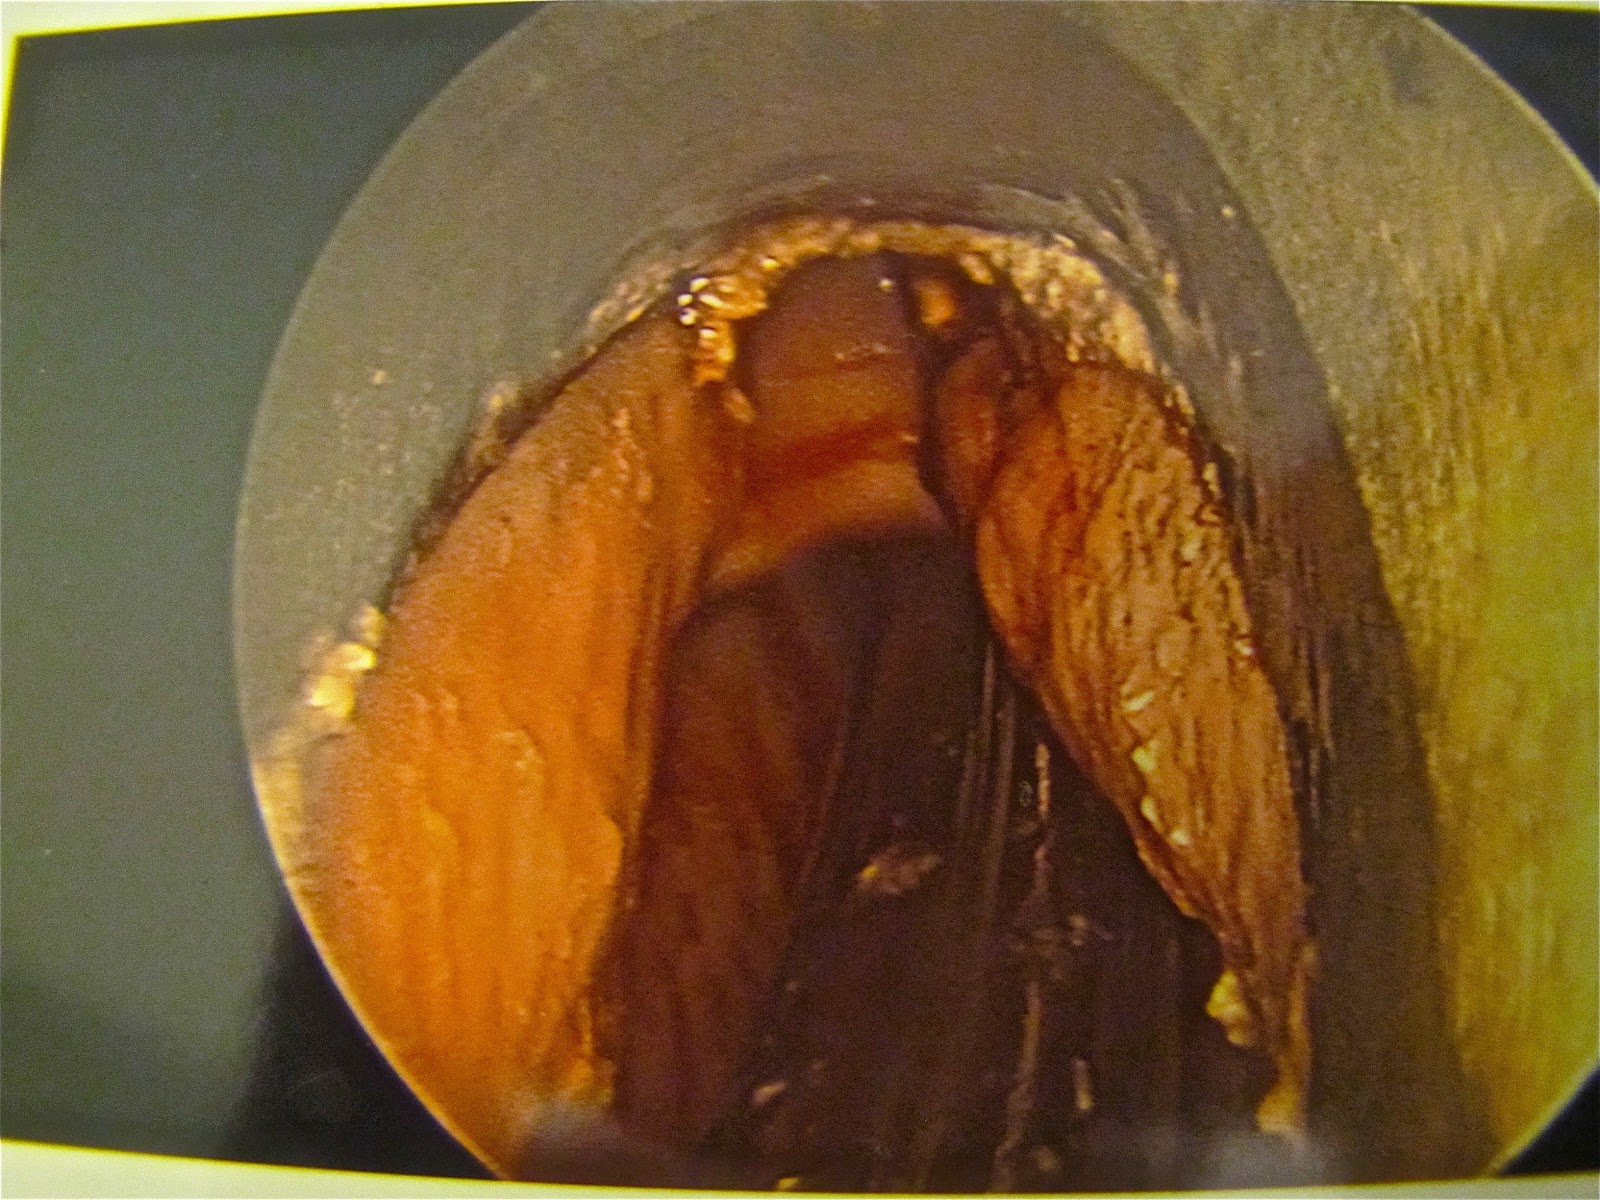

So here’s a photo of my generally irritated throat. There’s apparently nothing characteristically carcinogenic about this line of scabby tissue. The fact that it has appeared is enough to render it suspicious.

So Dr. H had the anesthesiologist put me under and slipped the knives in to excise some of the scab. Here you can see the scalpel and the rectangle of flesh ready to be pulled out and dropped into the vial.